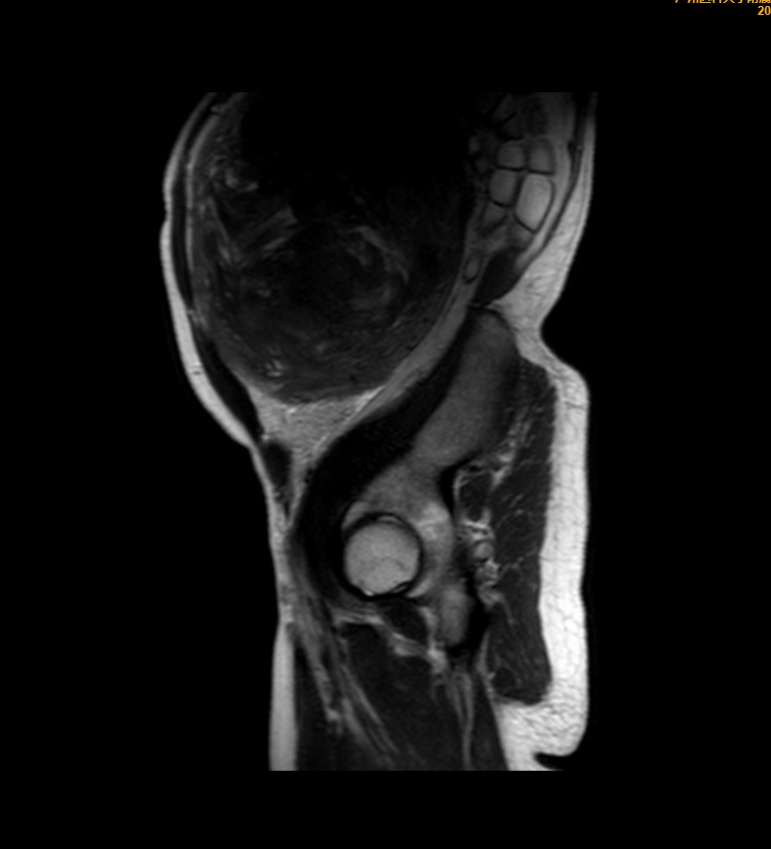

王女士术前影像检查

直到最近,因严重便秘影响生活,她到医院检查,才发现子宫肌瘤已经悄悄长到近30厘米,近乎一个篮球那么大!

医院团队为王女士实施了开腹全子宫切除术,切下来的子宫约莫有一个“篮球”那么大,重达4公斤!